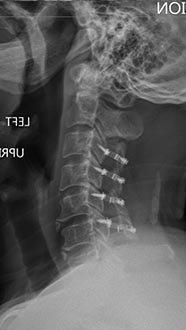

56 year old woman who presented with severe neck pain with numbness of both hands and balance problems due to severe cervical stenosis. Patient underwent C4 to C7 anterior cervical discectomy and fusion with complete resolution of her neurological symptoms.